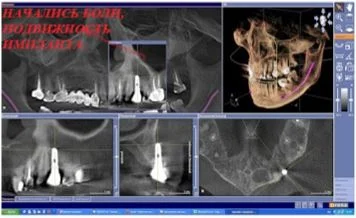

- Результаты исследования врач может просматривать на мониторе компьютера;

- Удобная программа обработки и просмотра изображения дает четкое понимание о состоянии проблемных зон, качестве и количестве кости, изогнутости корней зубов, анатомических особенностях расположения сосудов и нервов;

- Качественные трёхмерные снимки зубов дают возможность планировать весь процесс стоматологической реабилитации с высокой точностью и минимизировать процент возможных осложнений.

Как получить гарантированный результат имплантации? При помощи компьютерной томографии!